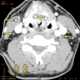

Laryngeal carcinoma

Laryngeal cancers are mostly squamous-cell carcinomas, reflecting their origin from the epithelium of the larynx. Cancer can develop in any part of the larynx. [Source: Wikipedia ]